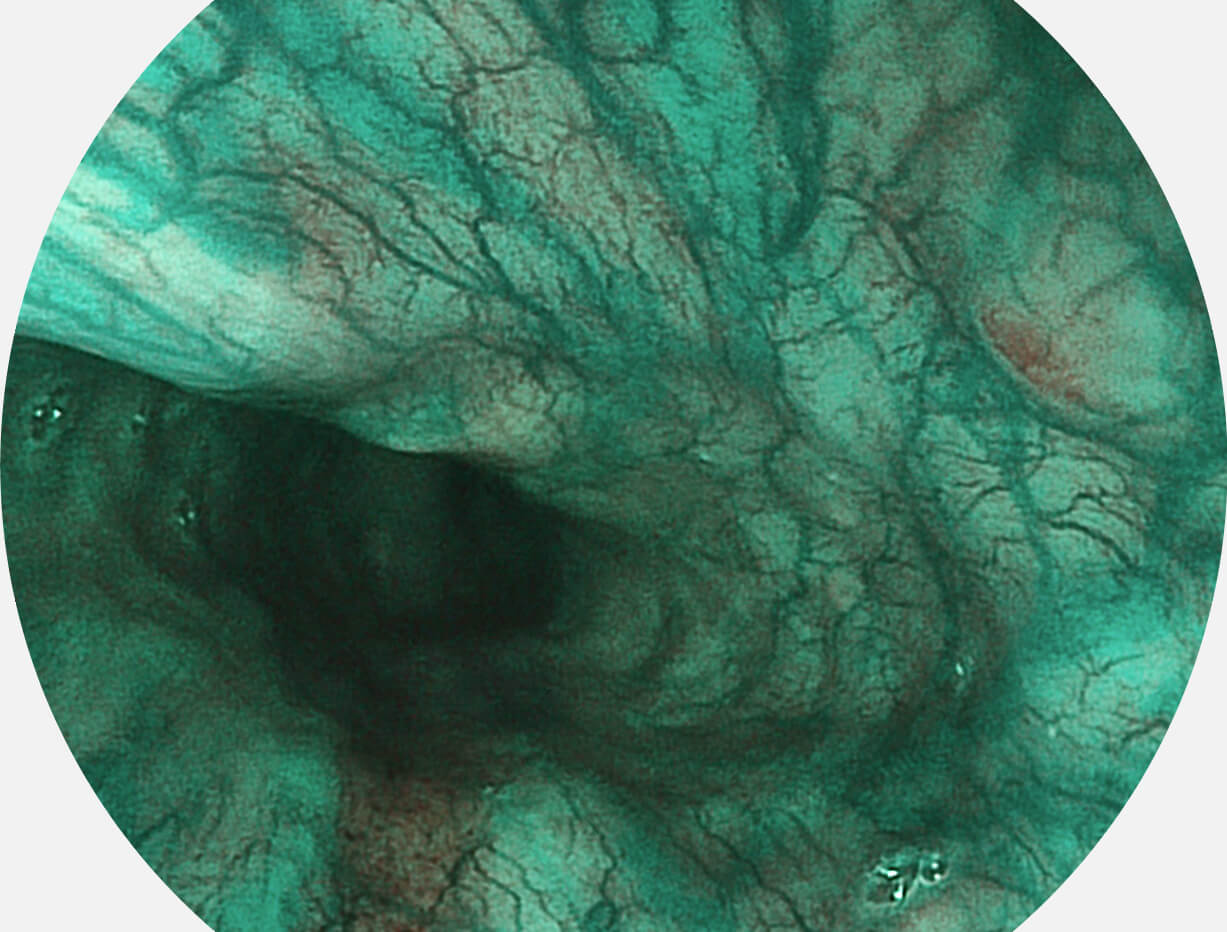

Versatile Intelligent Staining Technology, VIST

强调浅层黏膜结构的同时,保证照明亮度和提升浅层微血管与中层血管颜色对比度,病变边界更清晰。